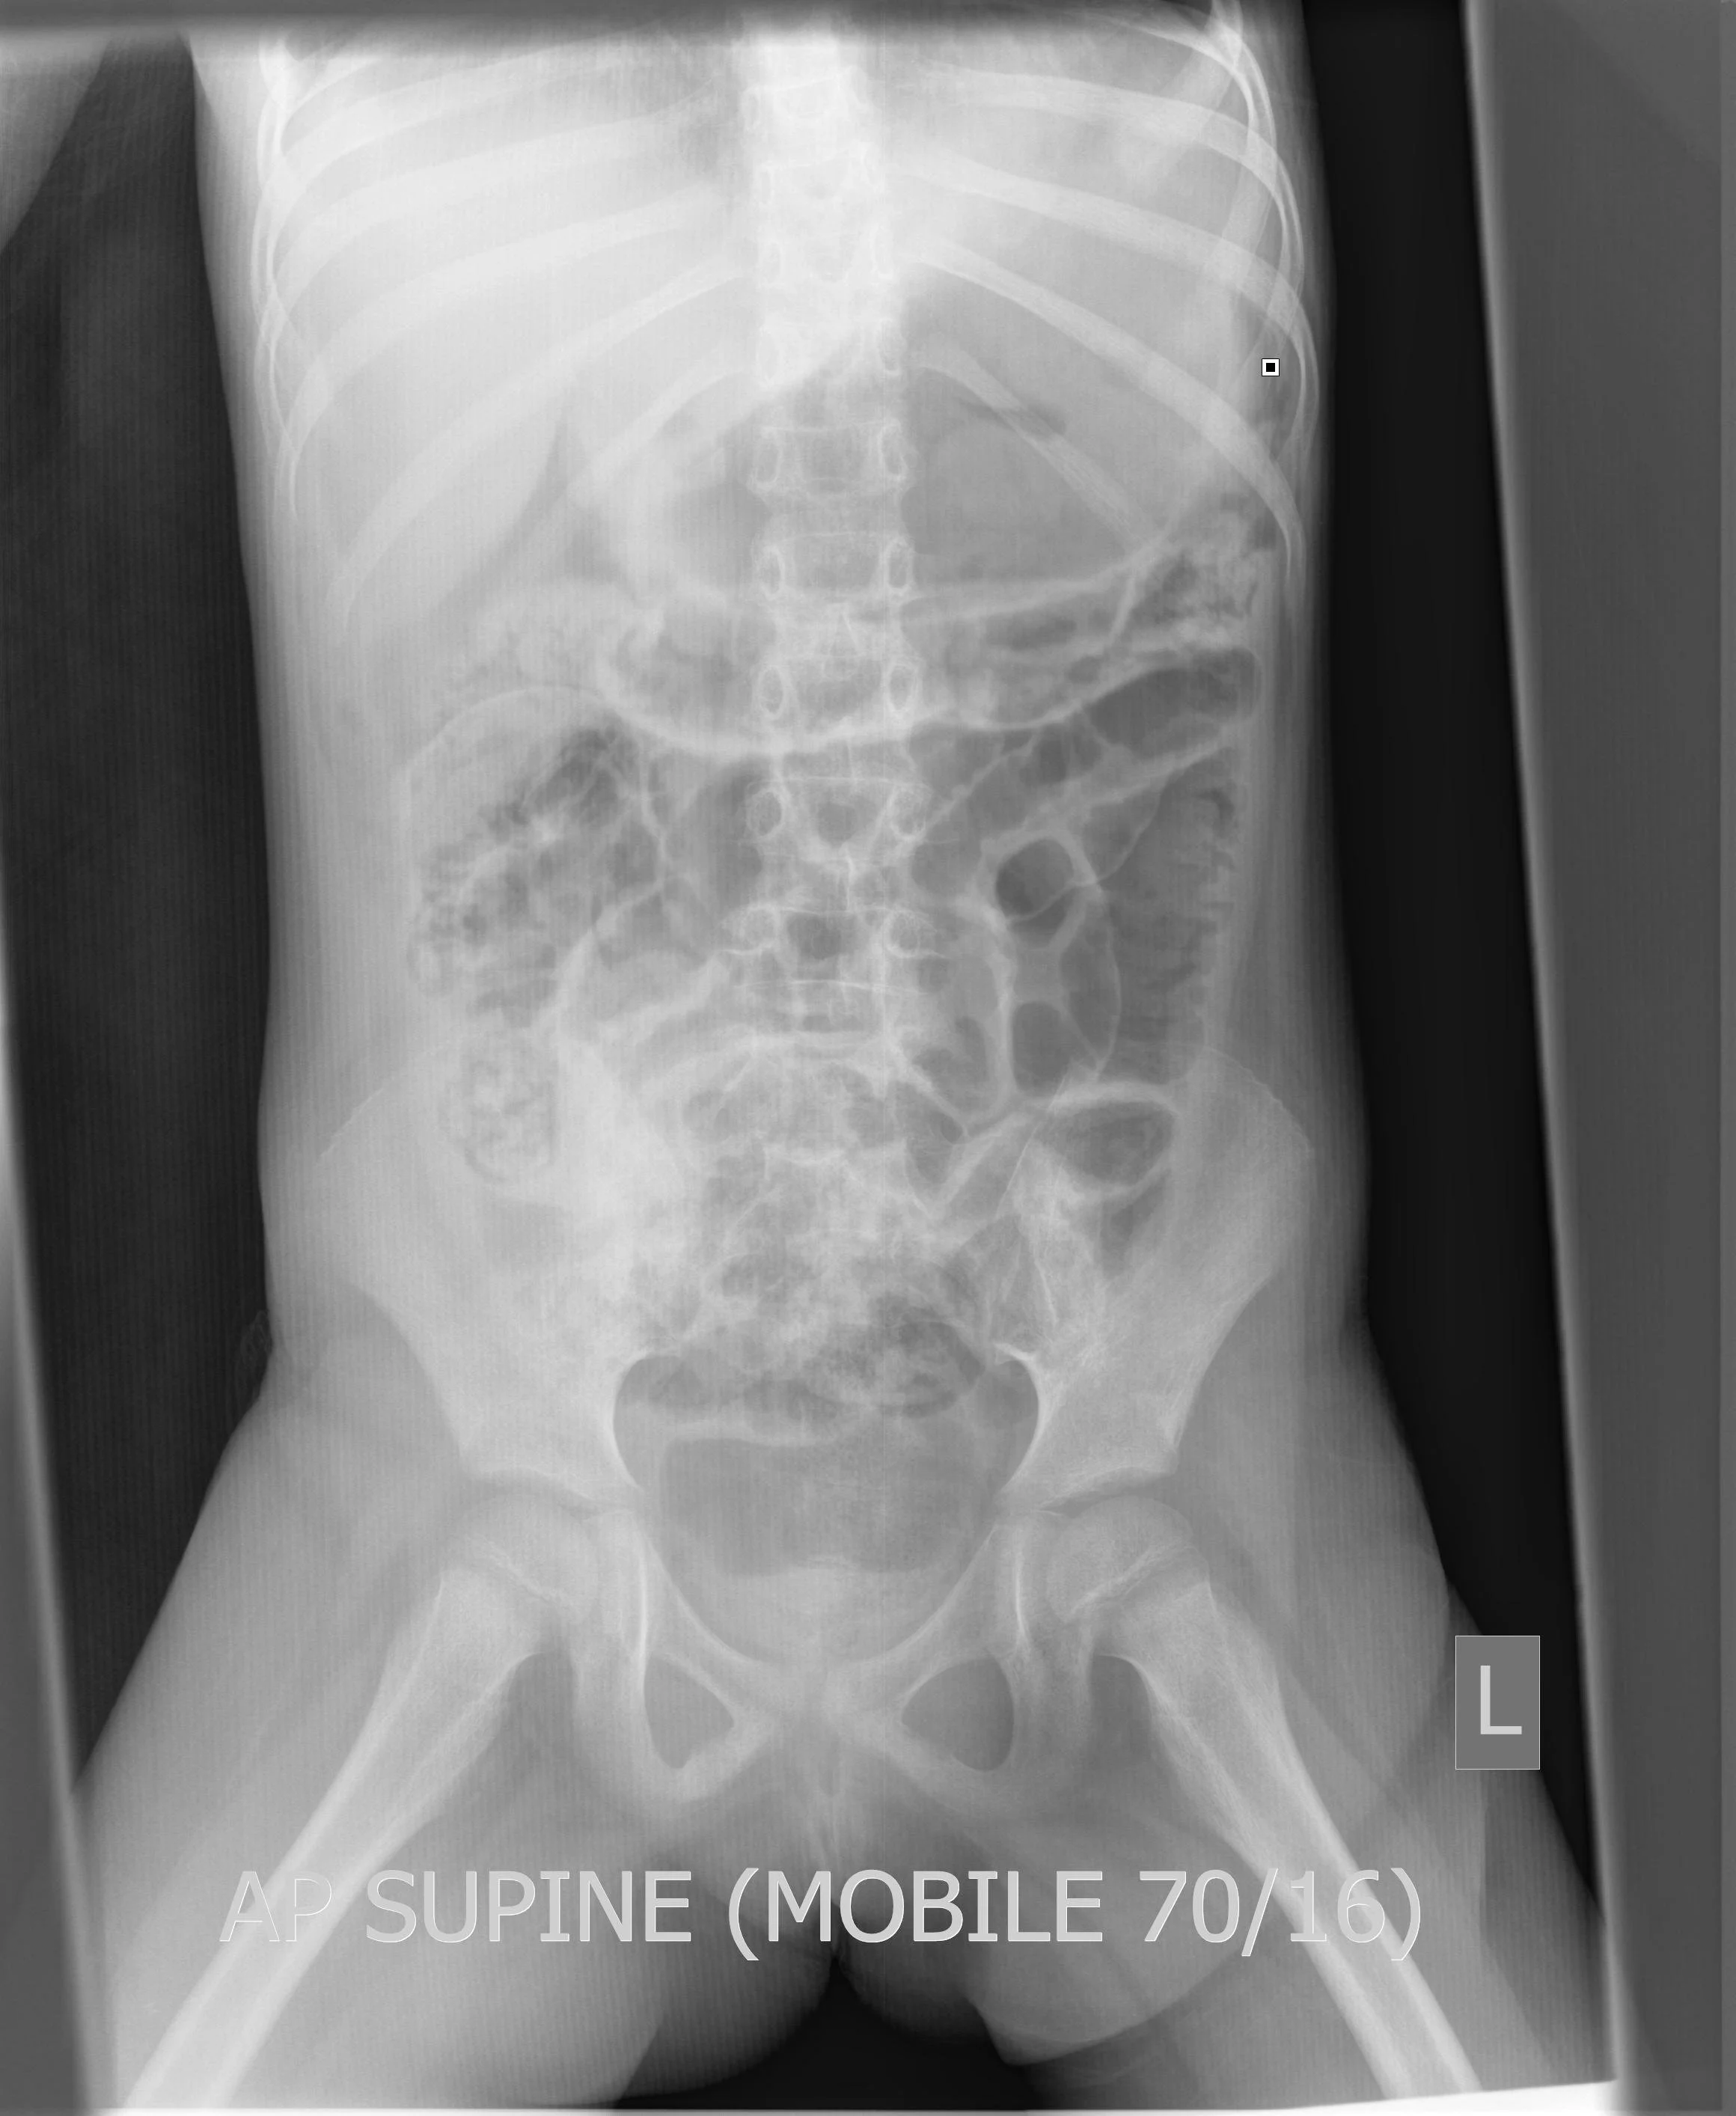

Rigler Sign (Double Bowel Wall Sign)

• Free gas/air is seen on both sides of the bowel causing the bowel wall to be very pronounced

• Indicates the presence of pneumoperitoneum